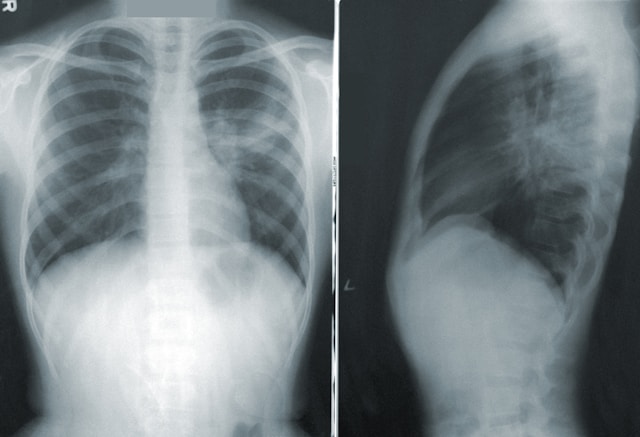

- Рентген грудної клітки при сухому плевриті зазвичай не показує специфічних змін — рідини немає, тому класичних затемнень не видно. Можна виявити лише непрямі ознаки: обмеження рухливості діафрагми на ураженій стороні, облітерію реберно-діафрагмальних синусів, високе стояння діафрагми, її нерівний контур. Найчастіше рентген допомагає виключити ексудативний плеврит і виявити основне захворювання (пневмонію, пухлину, ТЕЛА).